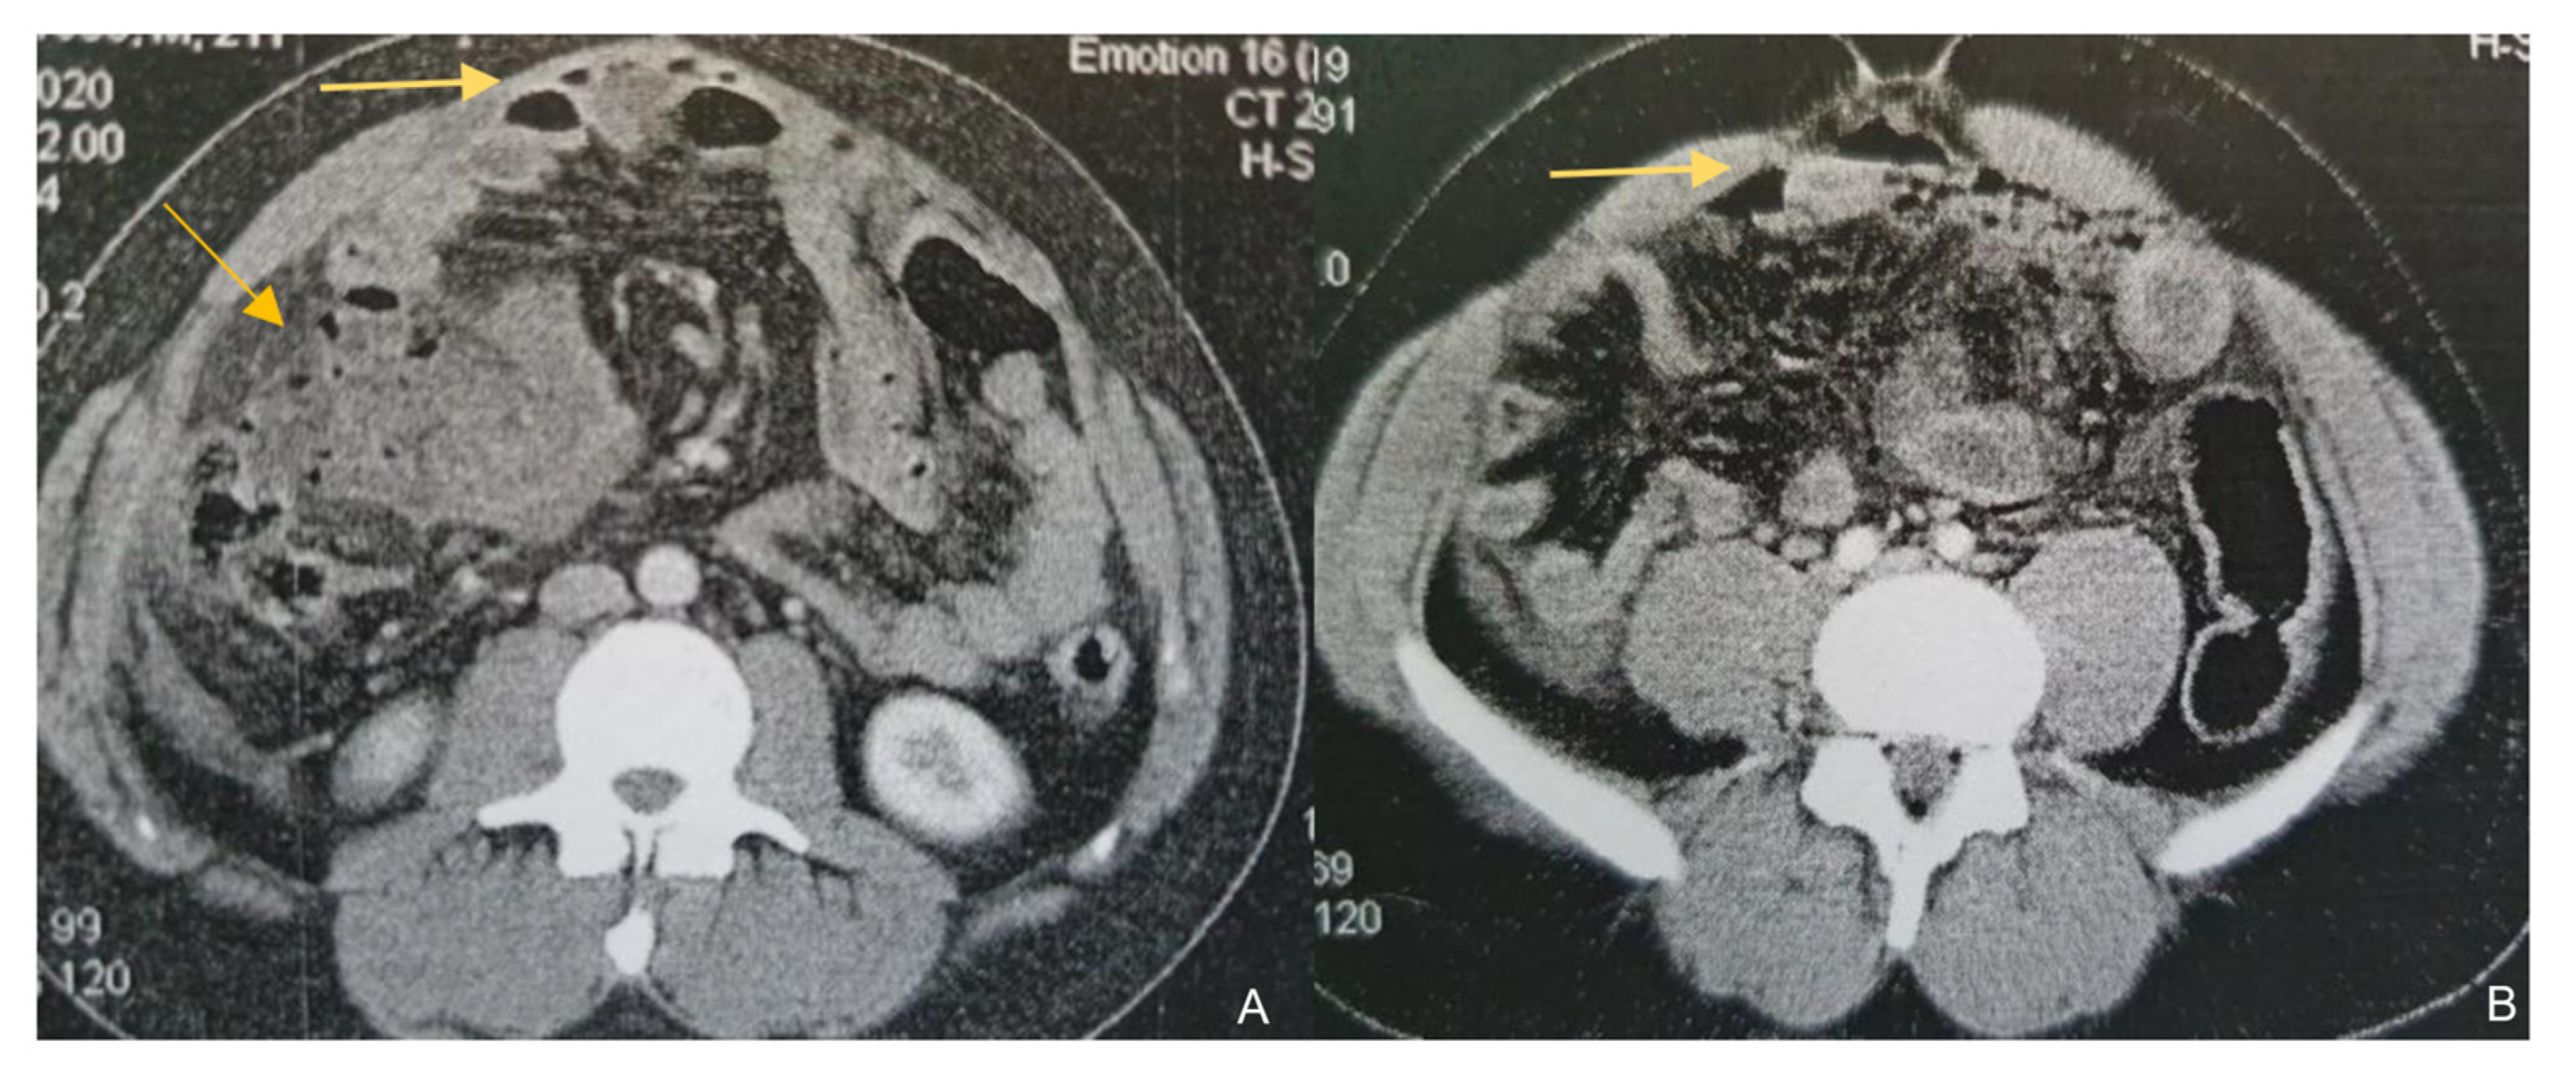

A 23-year-old male was referred to the surgical department from another hospital for further investigation and management of a high-output enterocutaneous fistula and possible short bowel syndrome. The patient’s medical history included several operations in the abdominal cavity due to recurrent incidents of intestinal perforations. His surgical problems had begun two years earlier, when he was admitted to the emergency department with acute epigastric pain, migrating within the next few hours to the right iliac fossa. Laboratory tests revealed leukocytosis (white blood cells (WBC) count 15.32 k/μL, neutrophils 87%) and increased C-Reactive Protein (CRP) at 1.9 mg/dL (normal range: <0.5 mg/dL). An abdominal Computed Tomography scan (CT scan) revealed free intra-abdominal air and pneumatosis of the descending and sigmoid colon (Figure 1). Thus, an exploratory laparotomy was performed, revealing generalized fecal peritonitis and a rupture on the antimesenteric wall of the sigmoid colon and confirming the diagnosis of gastrointestinal (GI) tract perforation. The hole was primarily sutured and the patient was discharged from the hospital on the 9th postoperative day, experiencing an uncomplicated postoperative period.

Figure 1.

Contrast-enhanced CT findings. Axial images of contrast-enhanced CT on presentation (A) and a subsequent episode of perforation (B). In both cases, a note is made of marked fat stranding, free intraperitoneal gas bubbles, and small bowel wall thickening, suggestive of small bowel perforation.